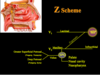

What is the blood supply and innervation like to the palate, including hard and soft palate?

- Greater palatine nerve and artery supply hard palate

- Lesser palatine nerve and artery supply soft palate

- Nasopalatine nerve supplies anterior 1/3 of hard palate

*The greater and lesser palatine arteries are branches off the descending palatine artery, which is one of the last branches off the Maxillary artery!

Which ganglion do the nerves supplying the palate arise from; and which nerve is the main one innervating the palate?

- Sensory nerves of the palate are branches of the Maxillary nerve (V2), which branch from the:

- Sphenopalatine Ganglion